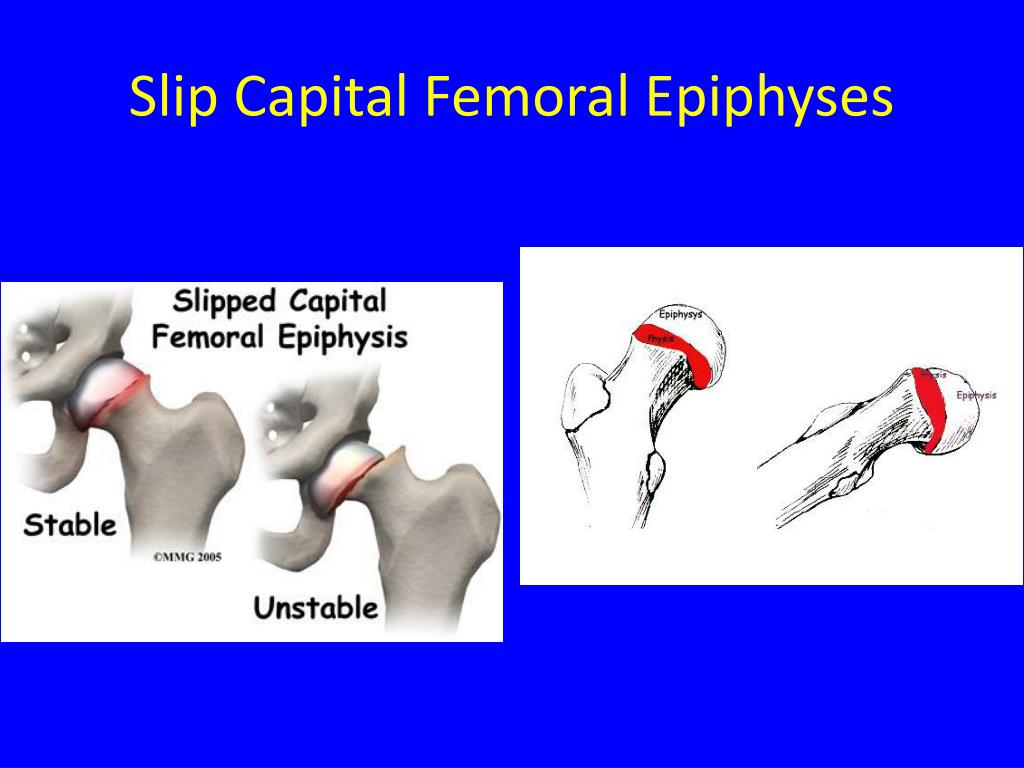

PPT - Slipped Capital Femoral Epiphysis SCFE PowerPoint Presentation

www.slideserve.com

www.slideserve.com

femoral capital epiphysis slipped scfe slip ppt epiphyses presentation powerpoint deformity